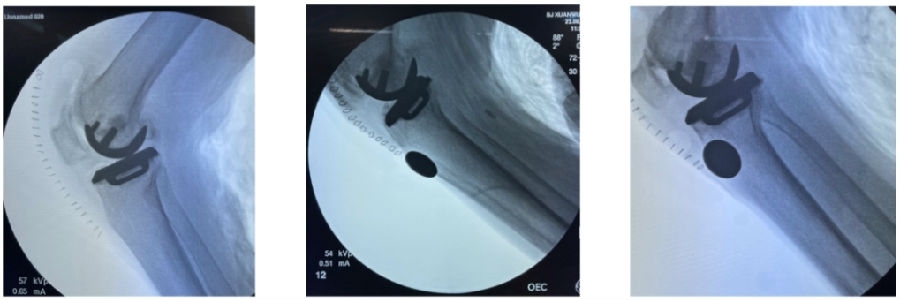

7、胫骨截骨

检查数据之后,进行分区截骨。垂直截骨注意避免后手抬高导致后方皮质过度切割。水平截骨在Z字拉钩保护下进行,最后截断内侧截骨槽的连接点。注意为避免锯的过程中出现震动导致的导板移位,需要在锯的过程中通过上面的按压点维持导板稳定。

在做了导板之后有一个突出的体会,就是会在取胫骨平台骨块时遇到很多困难,因为过去用传统工具时,可能后倾稍微大一点,由于后方切的比较深,后方关节囊会和骨块贴的比较紧,这时就要费很大力,将骨块从一个狭小空间内取出。但是做3D打印导板设计之后,且实施规划的比较好,基本就会很少遇到这样的困难了。

8、贴附股骨导板

将股骨导板置于对应的贴附区,沿按压点向后、向外下按压,确认位置贴附满意。术者通过按压点确保导板贴附,助手按照导针顺序顺着导针孔的方向固定导针。注意在导针有二次阻力突破即停止。同时要从各个角度确认导板贴附准确。

9、股骨钻孔

分别钻4毫米和6毫米桩孔。注意助手通过按压点维持导板稳定,并顺着导孔方向钻孔。

10、核查切骨与规划之间的吻合度

取下导板,取出骨块进行比对。注意对比厚度时要加上软骨的厚度如果吻合度有明显偏差,可以考虑徒手加截。

12、术后拍片

目前,笔者团队已经做了70多例,在早期探索过程中可能会出现一些问题,但是之后基本上都是比较好的,术后片子比较赏心悦目。